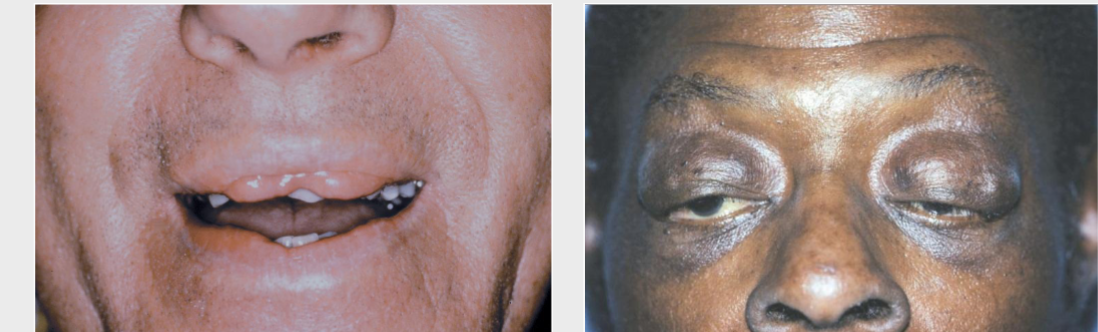

ascher syndrome

double lip, blepharochalasis (eyelid edema), and sometimes nontoxic thyroid enlargement

crouzon syndrome

craniosynostosis (premature cranial suture closure), ocular proptosis (bulging eyes), and clover leaf skull shape

apert syndrome

FUSED DIGITS, craniosynostosis, ocular proptosis, abnormal skull shape, maxillary hypoplasia